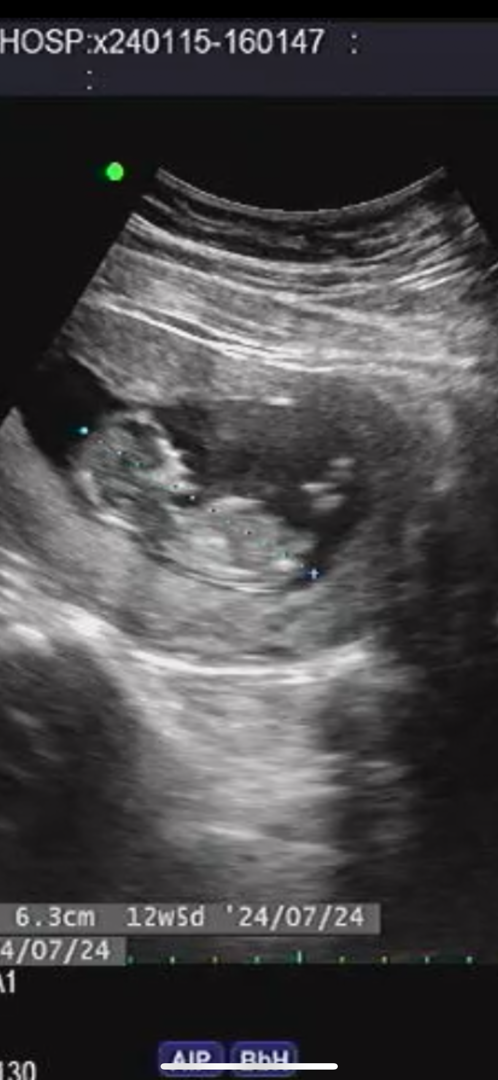

12주 4일차.. 딸이 맞을까욤..?

각도법 생각해보면 딸인거같은뎅 ㅠㅠ 맞을까요..?

으악 너무 흐려용 ㅠㅠ아직 모를것같아요

ㅠㅠ 여기 산부인과가 의사샘이 제왕을 진짜진짜 잘하시는데.. 초음파 화질이 넘 흐려요ㅠㅠㅠㅠㅠㅠ